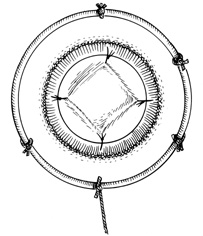

A Flieringa ring or McNeill-Goldmann blepharostat should be sutured to the globe to provide scleral support. One or two of the suture ends can be left long for fixation (Fig. 1). The center of the cornea and eight radial marks can be marked with a surgical pen and a radial keratotomy marker to guide suture placement. Alternatively, some trephines (e.g., Barron Recipient Trephine, Katena) are designed to create evenly spaced marks on the recipient cornea.

Fig. 1. Flieringa ring sutured to the globe. Twelve o'clock suture end is left long for fixation.